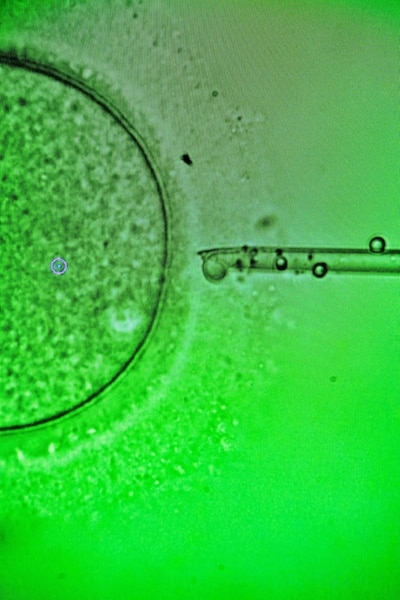

En el caso de los óvulos, tras extraer el líquido folicular del ovario, el embriólogo localiza uno entre la sustancia viscosa y lo limpia aspirándolo varias veces con una pipeta. Luego perfora su membrana externa para introducir el esperma, un procedimiento delicado que equivale a la cirugía de una célula.

El proceso robótico de Conceivable integra tecnología propia con técnicas de alta gama reservadas a los laboratorios más avanzados. El esperma se separa sin centrifugado, nadando por un laberinto creado por el robot, y es seleccionado por un algoritmo y detiene su movilidad con un láser. La IA identifica los óvulos y, al fecundar, un robot guía al espermatozoide con precisión ultrasónica hasta el óvulo. “La meta es ofrecer al mejor embriólogo del mundo, cada vez”, dijo Abram.